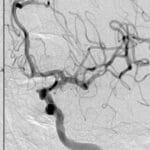

Cerebral Hyperperfusion Syndrome

Topic: Cerebral Hyperperfusion Syndrome Author: Ayah Bozeyeh Editor: Ihda Bani Khalaf Reviewer: Ethar Hazaimeh Keywords: Blood flow, Stroke, Pressure, Circulation, Autoregulation, Cerebrovascular disease Overview Cerebral Hyperperfusion Syndrome (CHS) is a rare but potentially devastating complication characterized by an abnormal and excessive increase in cerebral blood...